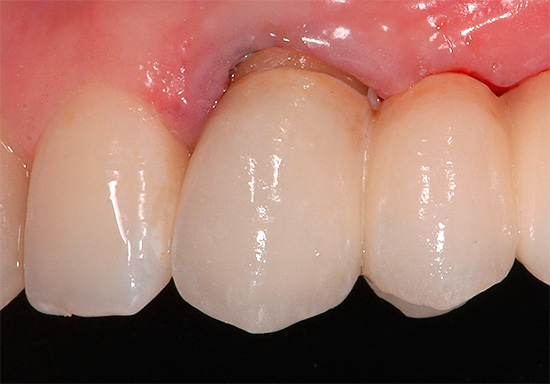

A foto abaixo mostra um exemplo de inflamação das gengivas em contato com as coroas: